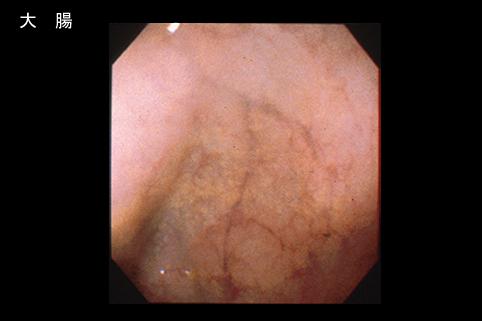

疾病(病理主体)的分类寄生虫疾患/其它

部位(按器官分)大肠/盲肠

检查方法内窥镜

肿瘤最大直径1~9